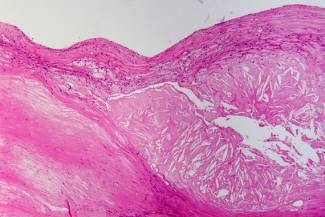

Placa aterosclerótica con vacíos de cristales de colesterol, macrófagos y fibrosis. (Foto: Patho)